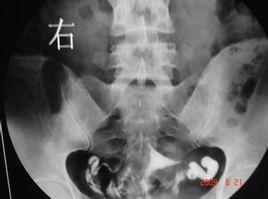

造影前排清大小便,消毒外陰、陰道和宮頸。在無菌操作下抽出造影劑7~10ml,因導管內須容納2mi,宮腔內約容3~5ml。將金屬導管或雙腔導管插入宮頸內阻緊。排出導管中氣泡,以防誤診為息肉或肌瘤。在透視下邊注入邊觀察,至子宮輸卵管均充盈即撮片;或在不透視下緩慢注入,至病人下腹脹即攝片。如果注入時有明顯阻力感或病人疼痛難受時,應停止注射,總注入量約5—10mi。如注入碘水劑,則連撮2片,相隔lO~15min,若注入碘油劑,第l片洗出觀察後,酌情攝第2片,待24小時後,擦洗陰道,清除可能殘留在陰道內的碘劑,再攝盆腔平片一張。若輸卵管通暢,則輸卵管內無油劑殘留,進入盆腹腔的油劑呈塗抹狀影像,子宮腔內殘留呈縱行條狀影,陰道內呈橫行條狀影,輸卵管傘部殘留呈香腸狀影。

(3)若套用金屬導管將造影劑充滿導管,排盡空氣,而後將導管插入子宮頸,堵緊宮頸外口,不至使造影劑外溢,在X線透視下觀察造影劑流經宮腔及輸卵管情況並攝片。在這個時期最好要攝片兩張,第一張掌握在造影劑充滿子宮及輸卵管全程的時候,造影劑經輸卵管進入盆腔內一少部分時攝第二張,如造影劑進入盆腔內彌散過多拍第二張,由於造影劑進入盆腔內彌散將影響對輸卵管具體情況的準確觀察,而後再次注入一定量的造影劑,順便拔出導管後讓患者適當走動,20分鐘左右待造影劑在盆腔內充分彌散時拍最後一張延遲造影片。若套用氣囊導管進行造影其過程和金屬導管造影過程大體相同。須要注意的是在進行子宮輸卵管造影檢查過程的拍片的抓拍時機,一定要掌握在造影劑流經輸卵管,保持一定壓力在造影劑流動的過程中拍片,只有這樣才能清楚的了解管腔的具體通暢情況。

2、在X線透視下觀察造影劑流經宮腔及輸卵管情況並攝片。在螢光透視下徐徐注入碘油。注入量第一次為3~5ml,觀察其進入子宮及流經輸卵管的情況,此時攝片一張。繼續推入碘油3~5ml,5~10分鐘後拍片。

4、收縮或輸卵管痙攣,可針刺合谷、內關穴或肌注藥品,24小時再在同樣部位拍攝第三張片,觀察腹腔內有無游離的碘化油。見邊界清楚的碘團,則考慮輸卵管粘連。輸卵管粘連堵塞有輕有重,粘連共分三度,輸卵管挾部粘連為一度:輸卵管與宮角結合部粘連為二度;輸卵管壺部與傘口粘連為三度。